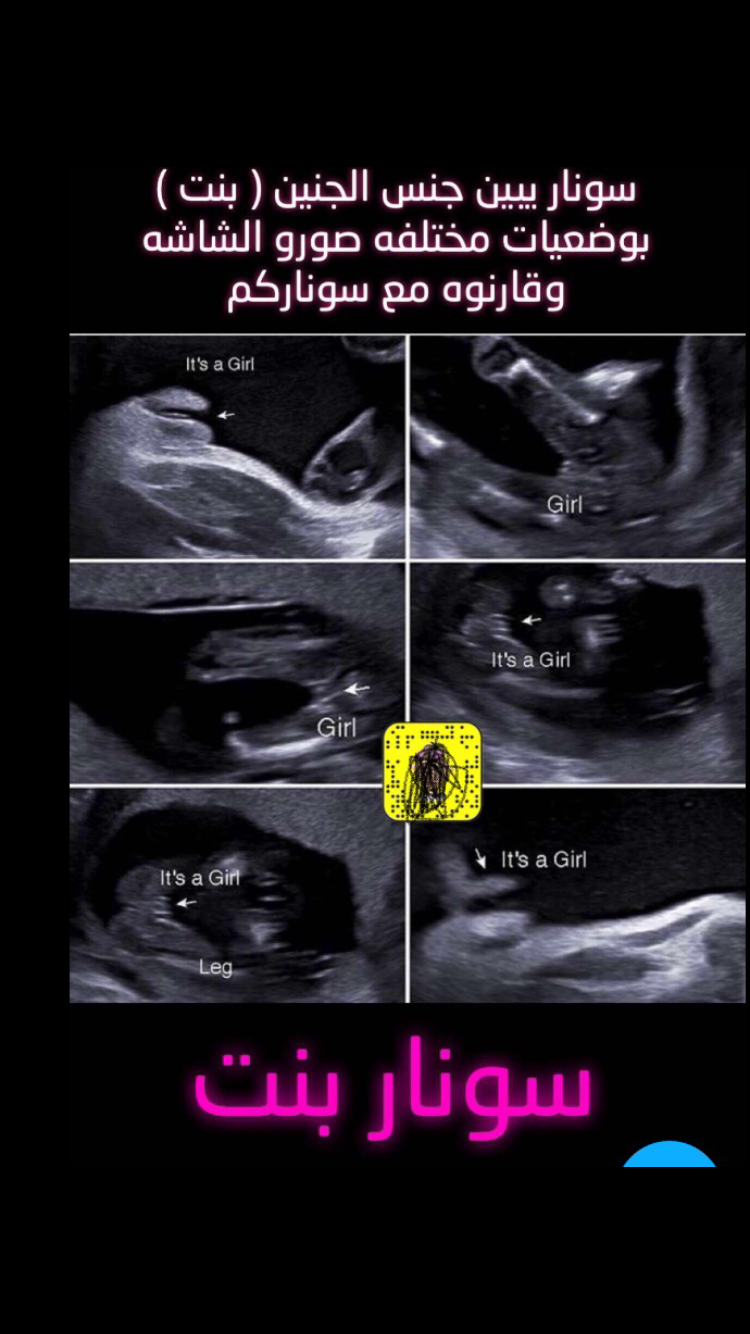

بنات شوفو هالصور

انا قارنتها بصوره سوناري طلع نفس سونار الولد